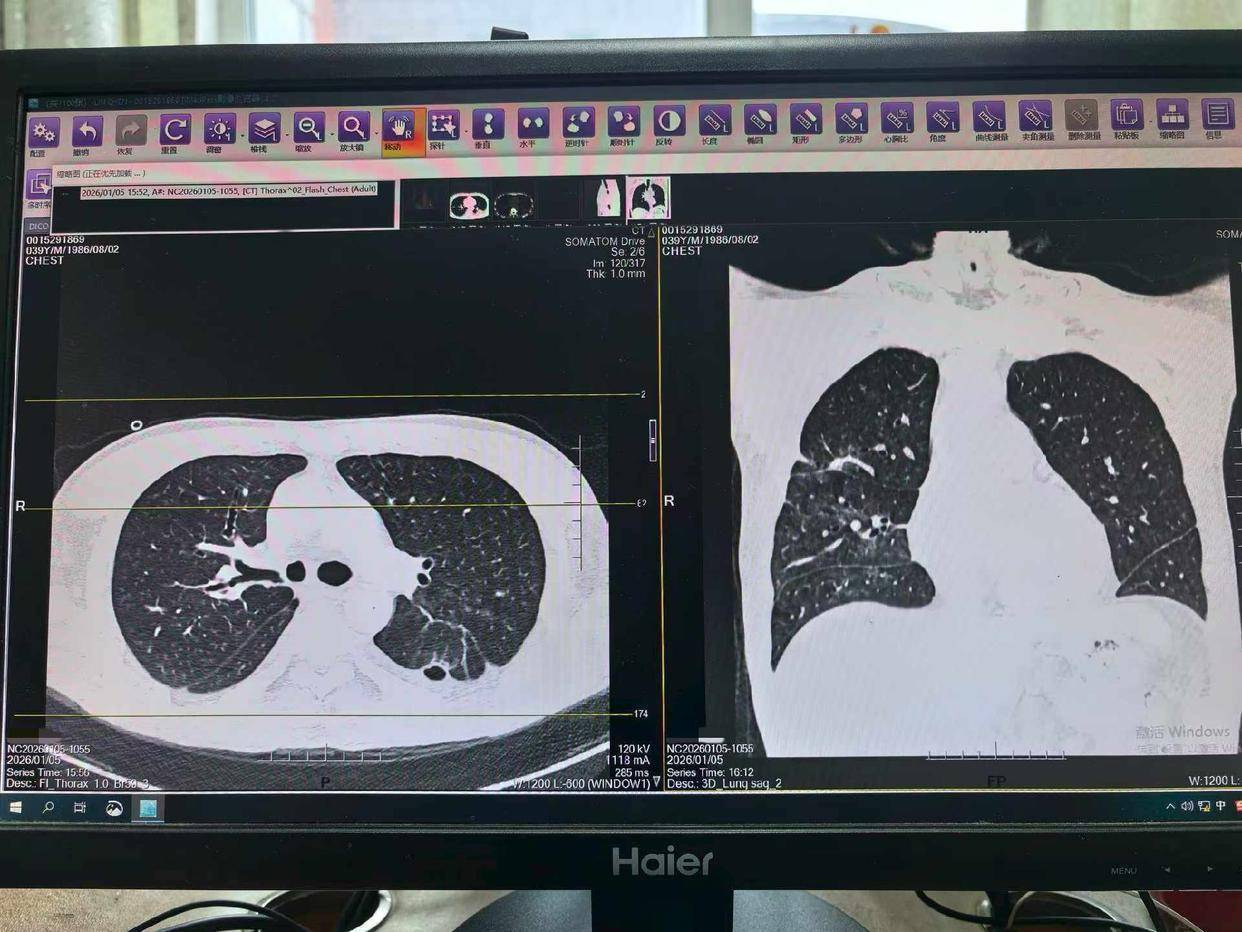

男子转至湘雅的时候,肺功能已近崩溃。“常规呼吸机已经难以维持生命体征,我们必须为他建立生命的‘体外通道’。”抢救团队当机立断,为男子启动了VV-ECMO(体外膜肺氧合),用这台“人工肺”替代衰竭的肺,为后续抢救争取宝贵时间。

在后续CT检查中,医生发现其左肺形成了肺脓肿,并且发生了支气管胸膜瘘。“这意味着感染灶持续存在,像一个定时炸弹。”周利平教授说。为了彻底清除病灶,经过多学科团队的慎重评估,最终为他实施了左下肺叶切除术。当感染的核心被切除,这场持久战终于迎来了转折点。术后约一周,患者即出院返渝。据随访,患者复查肺部CT显示恢复良好。

“面对如此复杂的危重症,单靠一个科室不可能完成,而湘雅医院综合救治能力是患者安全的最大托举。”湘雅医院急诊科李湘民主任介绍,76天里多学科团队如同精密运作的救援网络。急诊、血液、重症、胸外、呼吸、介入、输血等科室深度协作,进行了4次大型多学科会诊。支气管镜做了12次,胃镜6次,CT引导下的肺脓肿穿刺引流2次,前期还进行了2周持续血液净化治疗,“每一天都是在和死神赛跑”。